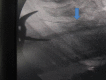

Accidental ingestion of foreign bodies is common in ENT practice. A very small number of ingested foreign bodies perforate the esophagus and even a smaller fraction of extra mucosal migration penetrates into the soft tissues of the neck. Most cases reported in the literature involve fish bones. If left untreated, they may result in life threatening complications. This case presents a patient with a metallic foreign body (metal wire) in the esophagus which migrated extraluminally into the prevertebral muscle of the neck and describes the difficulties encountered in removing the migrated foreign body. Intra-operative radiography using two metallic pointers was used to locate the exact position of the foreign body during exploration of the neck.